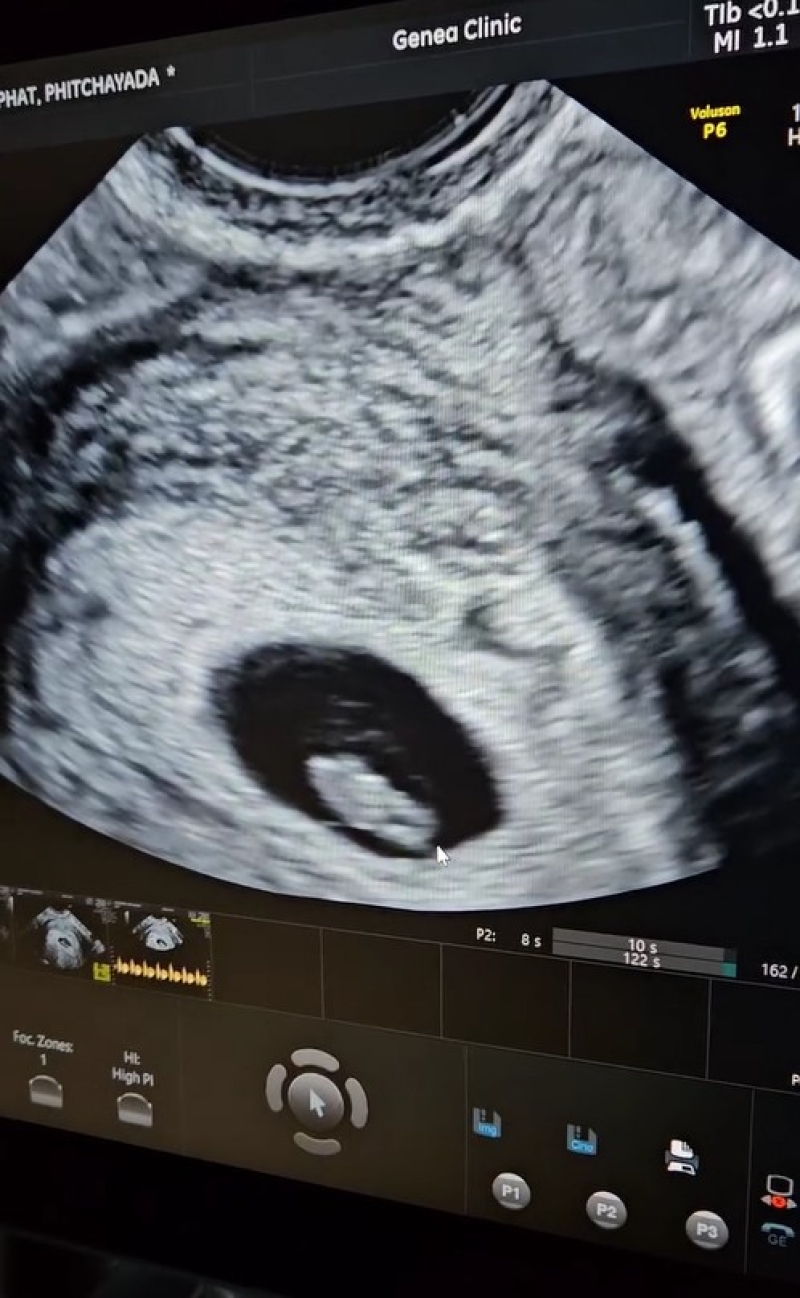

จากนั้นทั้งคู่เข้าสู่กระบวนการทางวิทยาศาสตร์ทันทีเพื่อมีพยานรักตัวน้อยด้วยกัน ซึ่งมีการใส่น้องเข้าไปเมื่อช่วงเดือนสิงหาคม ล่าสุดเม้าส์ได้เผยคลิปออัลตร้าซาวด์พร้อมเสียงหัวใจของลูกน้อยในครรภ์ภรรยา ระบุแคปชั่นว่า ได้ยินเสียงหัวใจหนูแล้ว #icsi